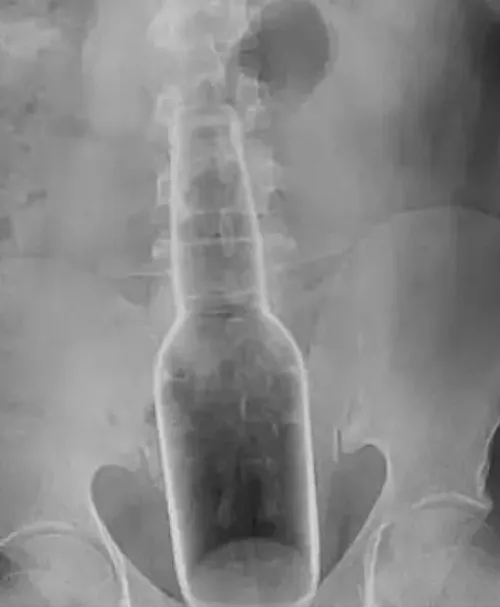

Een man krabt zijn rug met een 17 centimeter lang flesje die plotseling in zijn anus schiet

We hebben weer een bizar verhaal heur. Er is namelijk een man in China die per ongeluk een 17 centimeter lang flesje in zijn anus vond. Hij zou zichzelf op zijn rug krabben met het flesje die plots in zijn anus terecht kwam. Het zou je maar overkomen, zo plotseling. De doktors geloofde er in ieder geval geen hol van.

Mr Wen, zoals de man heet, is met een spoedoperatie gered van zijn anale pijn. Want de beste man kreeg hem erzelf niet meer uit. Stel je het moment voor dat die vast zit en je naar de doktor moet, haha. Maar goed, hij ging naar het Dongguan-ziekenhuis in de provincie Guangdong in het zuiden van China, nadat hij het moeilijk vond om te lopen met het 5 cm brede object dat zich in zijn achterwerk bevond. De operatie duurde niet lang en de man stond op dezelfde dag weer buiten. Het bleek dat de fles was gebruikt om vloeistof vast te houden die werd gebruikt als een traditionele Chinese muggenspray en jeukspeen. Een typisch gevalletje van 'i slipped'?